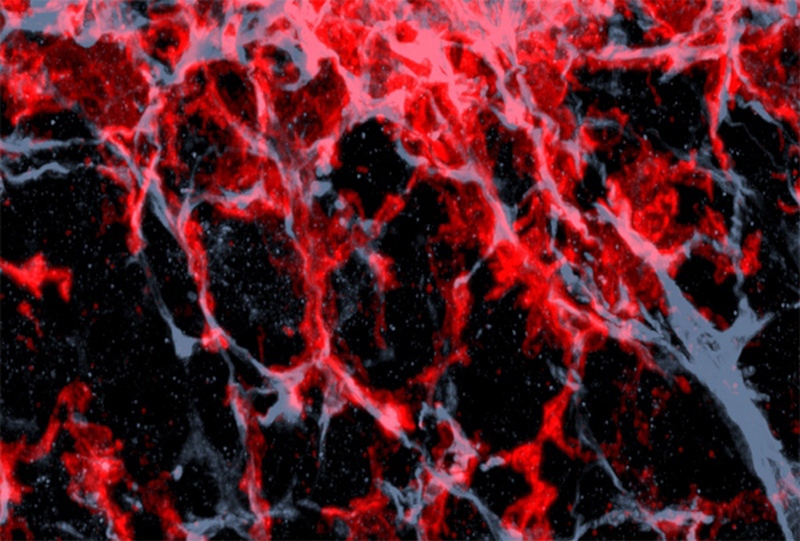

I macrofagi sono noti per essere le “cellule spazzino” del sistema immunitario, ma recentemente si è capito che possono essere riprogrammate quando interferiscono con il microambiente che si crea quando le cellule sane diventano tumorali. In questa loro nuova identità, resa possibile dalla proteina chiamata ERK5, i macrofagi diventano alleati dei tumori e li aiutano a crescere. Di conseguenza la proteina ERK5 potrebbe diventare il bersaglio di futuri farmaci, come indicano i test che nei topi sono riusciti a bloccare la crescita dei tumori: eliminandola è possibile ridurre il numero dei macrofagi e bloccarne l'azione.